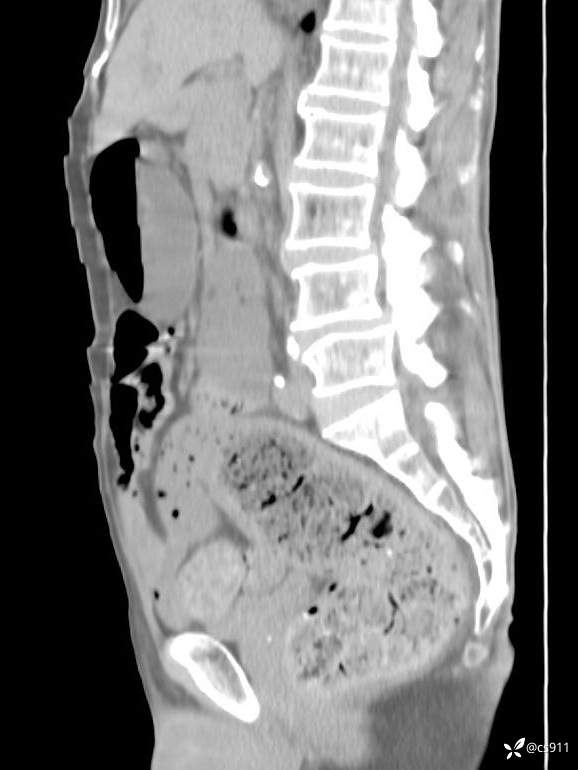

急腹症之急诊CT,原因?答案公布

男,77岁,腹痛、腹胀伴恶心呕吐1天。呕吐胃内容物,非喷射性呕吐,有咖啡色样胃内容物,诉有胃穿孔病史。查体:全腹平,下腹部压痛,全腹无反跳痛,叩诊呈浊音,移动性浊音阴性,肠鸣音减弱,1-2次/分。肛检:直肠未扪及明显肿物,可触及大量粪块。

血淀粉酶(AMY) HH 1859 U/L 35-135

癌胚抗原(CEA) H 27.44 ng/ml 0-5